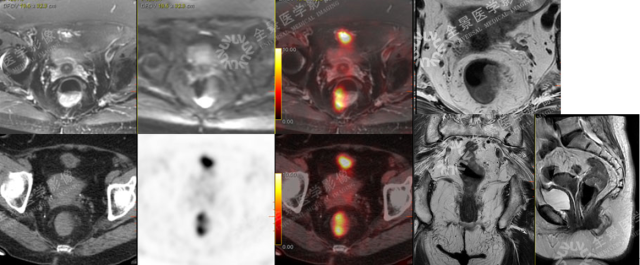

女性,78 岁,大便带血月余,肠镜活检病理:直肠癌,行临床分期。

T3aN0M0,MRF(-),EMVI(-)

案例二